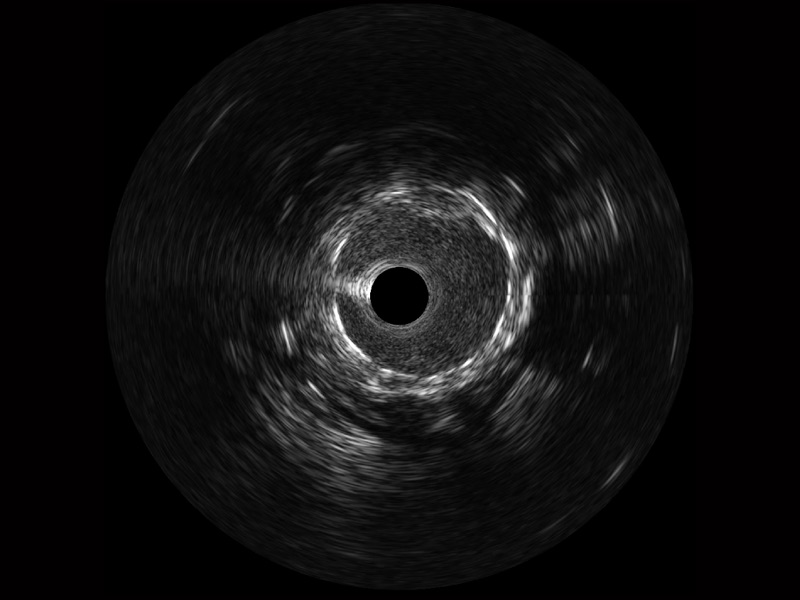

開(kāi)立寬頻IVUS圖像

對(duì)比傳統(tǒng)IVUS導(dǎo)管成像,開(kāi)立寬頻IVUS圖像的近場(chǎng)支架梁顯影更細(xì)膩,遠(yuǎn)場(chǎng)中膜外血管仍清晰可辨,兼顧遠(yuǎn)中近,兼顧分辨力與穿透深度